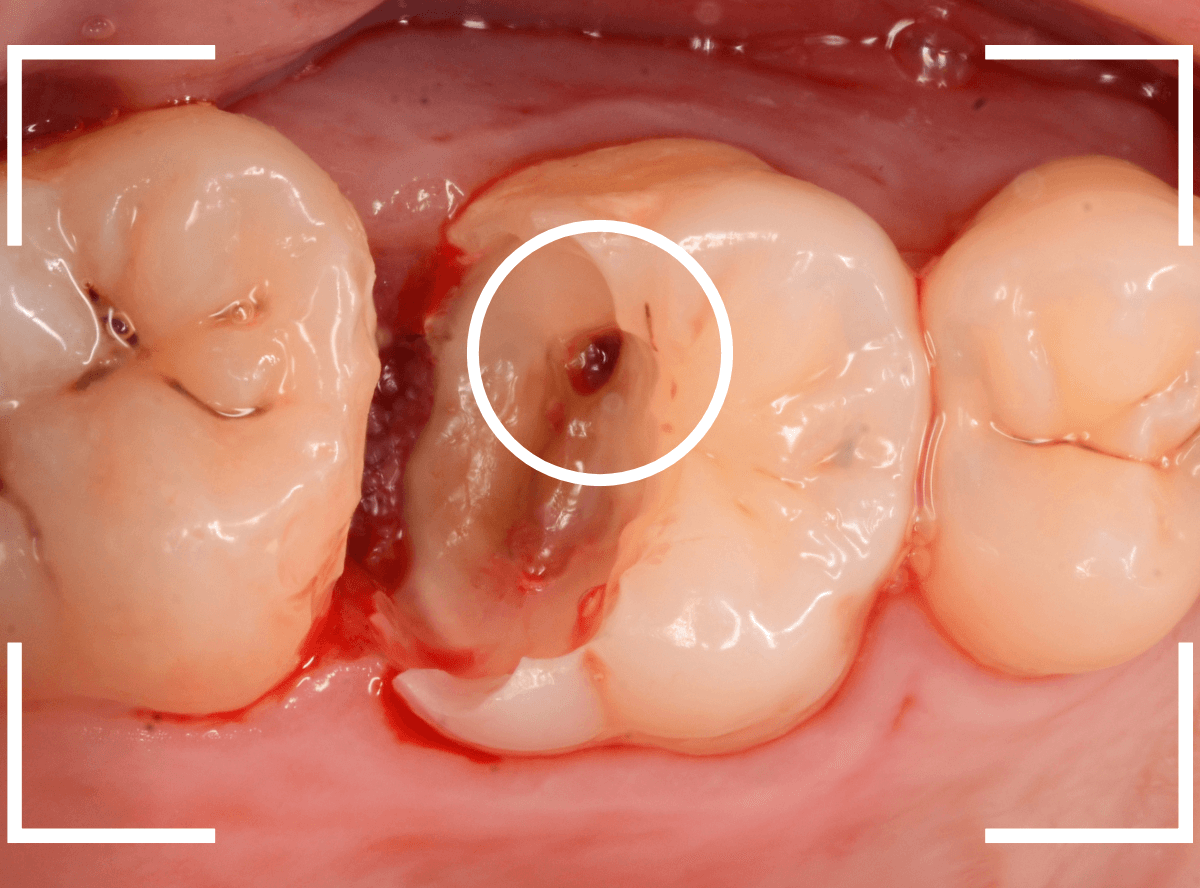

麻酔をして、治療を開始します。

レジンを外すと、中から出血してきました。

これは、歯のスキマに歯肉が入り込んでしまったために起こってしまったものです。

おそらく、随分前から虫歯が進行していたと思われます。

止血しながら、電気メスで歯の中に入り込んだ歯肉を除去します。

虫歯と入り込んだ歯肉でぐちゃぐちゃになっている状態でした。

慎重に全ての虫歯を除去したところです。

〇部が神経の入り口が見えているところです。

神経を保護する処置をして、しばらく経過観察しますが、痛みが出て神経を除去する必要が出る可能性も高いです。